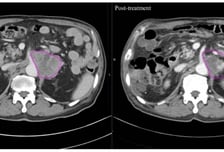

"암세포만 골라 죽였다"…방사선보다 더 효과 보인 이 치료법

몸속 온도를 '암이 싫어하는 온도(40~43도)까지' 끌어올려 암을 죽이는 '고주파 온열치료'는 새로운 암 치료법 중 하나로 꼽힌다. 이런 가운데 고주파 온열치료를 받은 암 환자들이 방사선 치료받은 환자들보다 암 덩어리가 더 빠르고 효과적으로 줄어든 사실이 국내 '빅5' 병원인 서울성모병원의 연구 결과로 나와 눈길을 끈다. 24일 국제바이러스연구연합(IVRA) 조직위원회에 따르면 장홍석 서울성모병원 방사선종양학과 교수 연구팀은 2019년 1월부터 2022년 3월 말까지 고온 온열치료 환자 20명과 방사선 단독 치료 환자 20명 등 전이성 복부 림프절 치료 환자 총 40명을 대상으로 컴퓨터 단층촬영(CT) 이미지를 모았다. 그리고서 치료 전후 종양 괴사의 변화를 관찰하는 지표(하운스필드 단위·Hounsfield Unit·HU)값의 변화를 비교해 치료 효과를 평가했다. HU는 CT(컴퓨터 단층촬영)에서 CT 영상의 픽셀마다 부여되는 밀도 값으로 조직의 밀도를 수치화한 것이다. 각 조직이